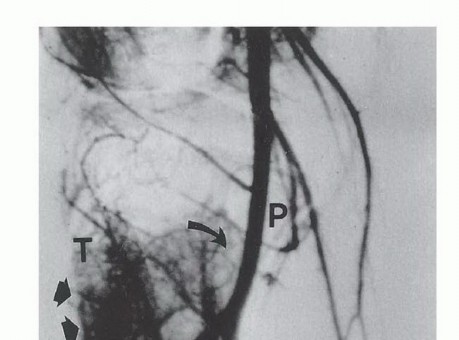

تصوير الأوعية الدموية

يُستخدم تصوير الأوعية ثنائي المستوى (Angiography) لتقييم الشرايين المحلية، خاصة إذا كشف التصوير المقطعي المحوسب عن امتداد الورم إلى الأنسجة الرخوة الخلفية. تُستخدم الرؤية الأمامية الخلفية لتقييم تفرع الشريان المأبضي، مع التركيز بشكل خاص على سلامة الشريان الظنبوبي الخلفي، والذي قد يكون المصدر الوحيد لإمداد الدم للساق بعد الاستئصال.

تُعد الرؤية الجانبية ضرورية لتقييم المسافة بين قصبة الساق والحزمة الوعائية العصبية. على سبيل المثال، غالباً ما تفصل العضلة المأبضية كتلة الورم الخلفية عن الأوعية الدموية. ينعكس هذا كمسافة واضحة في تصوير الأوعية الجانبي، ويشير إلى وجود هامش استئصال كافٍ. غالباً ما يكون ربط الشريان الظنبوبي الأمامي ضرورياً. قد يتأثر الشريان الشظوي بالأورام التي تشغل حجرة خلفية كبيرة. في المرضى الشباب، يمكن ربط اثنين من الأوعية الرئيسية دون تعريض إمكانية بقاء الطرف حياً وظيفياً للخطر. نادراً ما يتأثر الشريان الظنبوبي الخلفي بالورم.

صورة توضيحية للشريان المأبضي.

صورة وعائية جانبية للشريان المأبضي تظهر المسافة بين الورم والحزمة الوعائية العصبية.